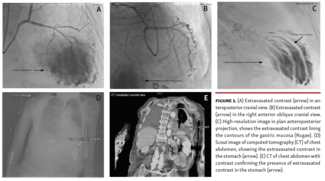

Tim A. Fischell, MD, FACC, FSCAI; Mandeep Singh Randhawa, MD

J INVASIVE CARDIOL 2021;33(6):E489. doi:10.25270/jic/20.00743 Key words: complications, contrast extravasation, coronary angiography, heart failure A 79-year-old woman presented with new-onset heart failure. She had pleural effusion,...